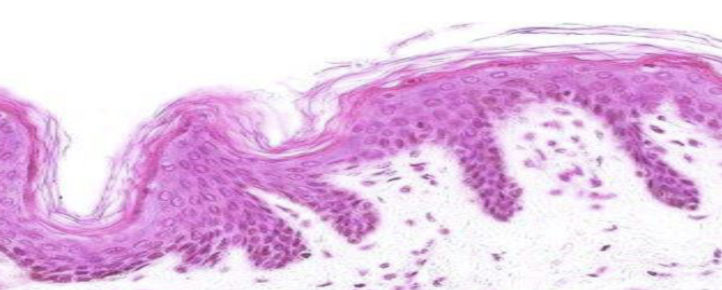

Clasifique tejido epitelial

estratificado queratinizado

Indique sitio anatómico donde se encuentra

piel delgada

Forma de sus células

plano

Número de capas

estratificado

Indique función

protección